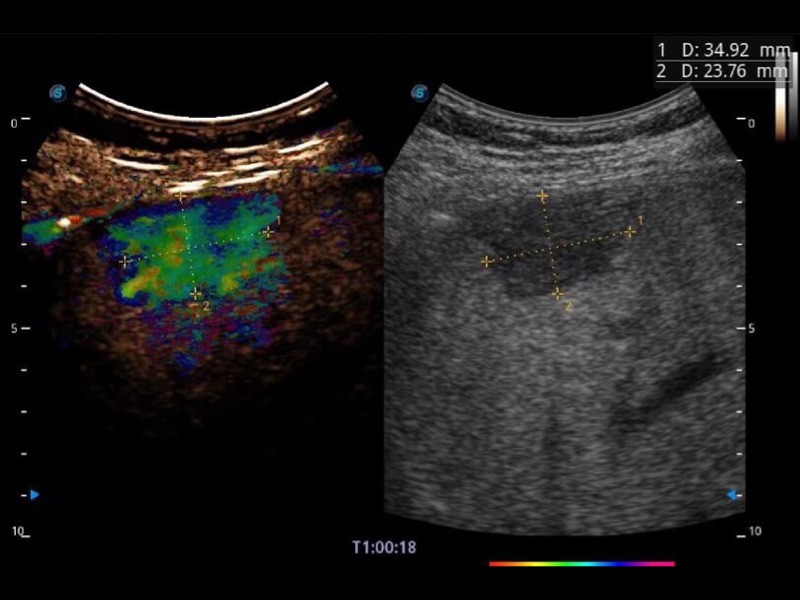

Klinisches Vertrauen verlangt hohe Leistung und fortschrittliche Werkzeuge. ProPet wurde für abdominelle und oberflächliche Untersuchungen mit fortschrittlichen Werkzeugen entwickelt, die Tierärzten in der täglichen klinischen Praxis helfen wie nie zuvor.

Ausgestattet mit dem gesamten Sortiment an Phased-Array-Schallköpfen von SonoScape (S1-5, 7P-A, 8P1), hochentwickelter Verarbeitungstechnologie und modernsten kardiologischen Tools bietet die ProPet-Serie Tierärzten eine umfassende ABklärung der Herz- und Myokardfunktionen.